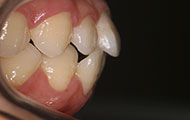

我的牙齿左侧上下植入支抗钉,这是为了更好的矫正,一点也不疼哦,所以说别看都是一样的牙套,不一样的医生做效果还是有区别的,所以选择去哪里的时候,还是要好好看一下效果和医生资质这些